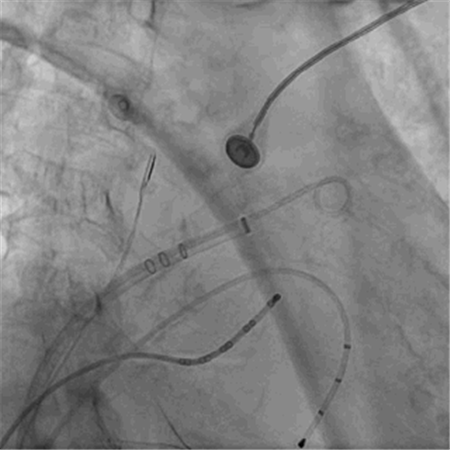

左心耳造影